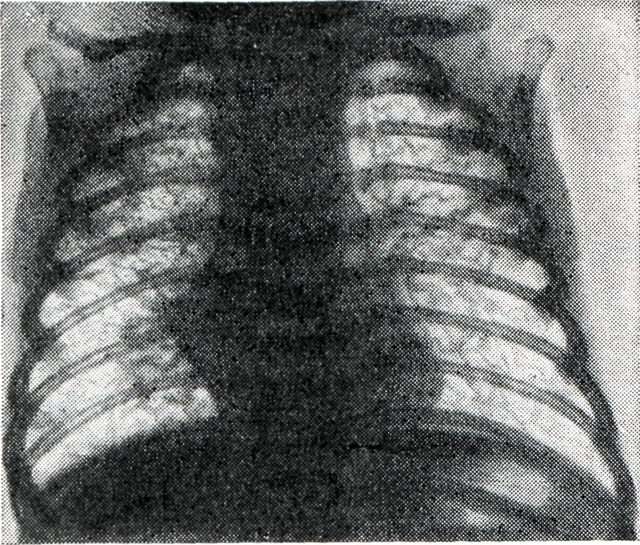

Рентгенограмма грудной клетки больного с синдромом Вильсона — Микити: на фоне эмфиземы лёгких выражено усиление лёгочного рисунка в области корней.

Иногда наблюдается эозинофилия до 15% . Биохимические, бактериологические, вирусологические, серологические данные без особенностей. В течение болезни развивается дыхательный аци¬доз, снижается насыщение кислоро¬дом крови. Приблизительно на 3-й неделе появляются типичные для В.— М. с. изменения на рентгенограммах: базальная и распространённая эмфизема, симметричное усиление лёгочного рисунка в области корней (рисунок), утолщение интерстициальных перегородок, увеличение размеров сердца; типична «нодозно-ретикулярная сетка» — рентгенологическое отображение незрелой лёгочной ткани. Сетка состоит из теней нередуцированной и содержащей эмбриональные волокна соединительной ткани, между которыми расположены заполненные воздухом незрелые концевые отделы дыхательных путей. Сетка включает очаги — тени нерасправившихся постнатально долек лёгких и мелких неразвитых сосудов. Присоединение расплывчатых затемнений указывает на развитие отечно-геморрагического синдрома, который резко ухудшает прогноз заболевания. Постепенное созревание лёгочной ткани, отмечаемое рентгенологически по восстановлению нормальной структуры лёгочного рисунка, ведёт к благоприятному исходу.